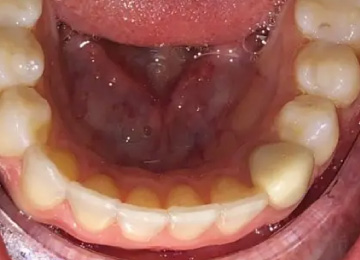

Капа для зубов: фото До и После

Фото ДО

Фото ПОСЛЕ

Наведите для просмотра

Капа для выравнивая зубов